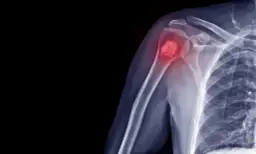

- Silne bóle kostne, szczególnie kręgosłupa

- Powiększenie węzłów chłonnych